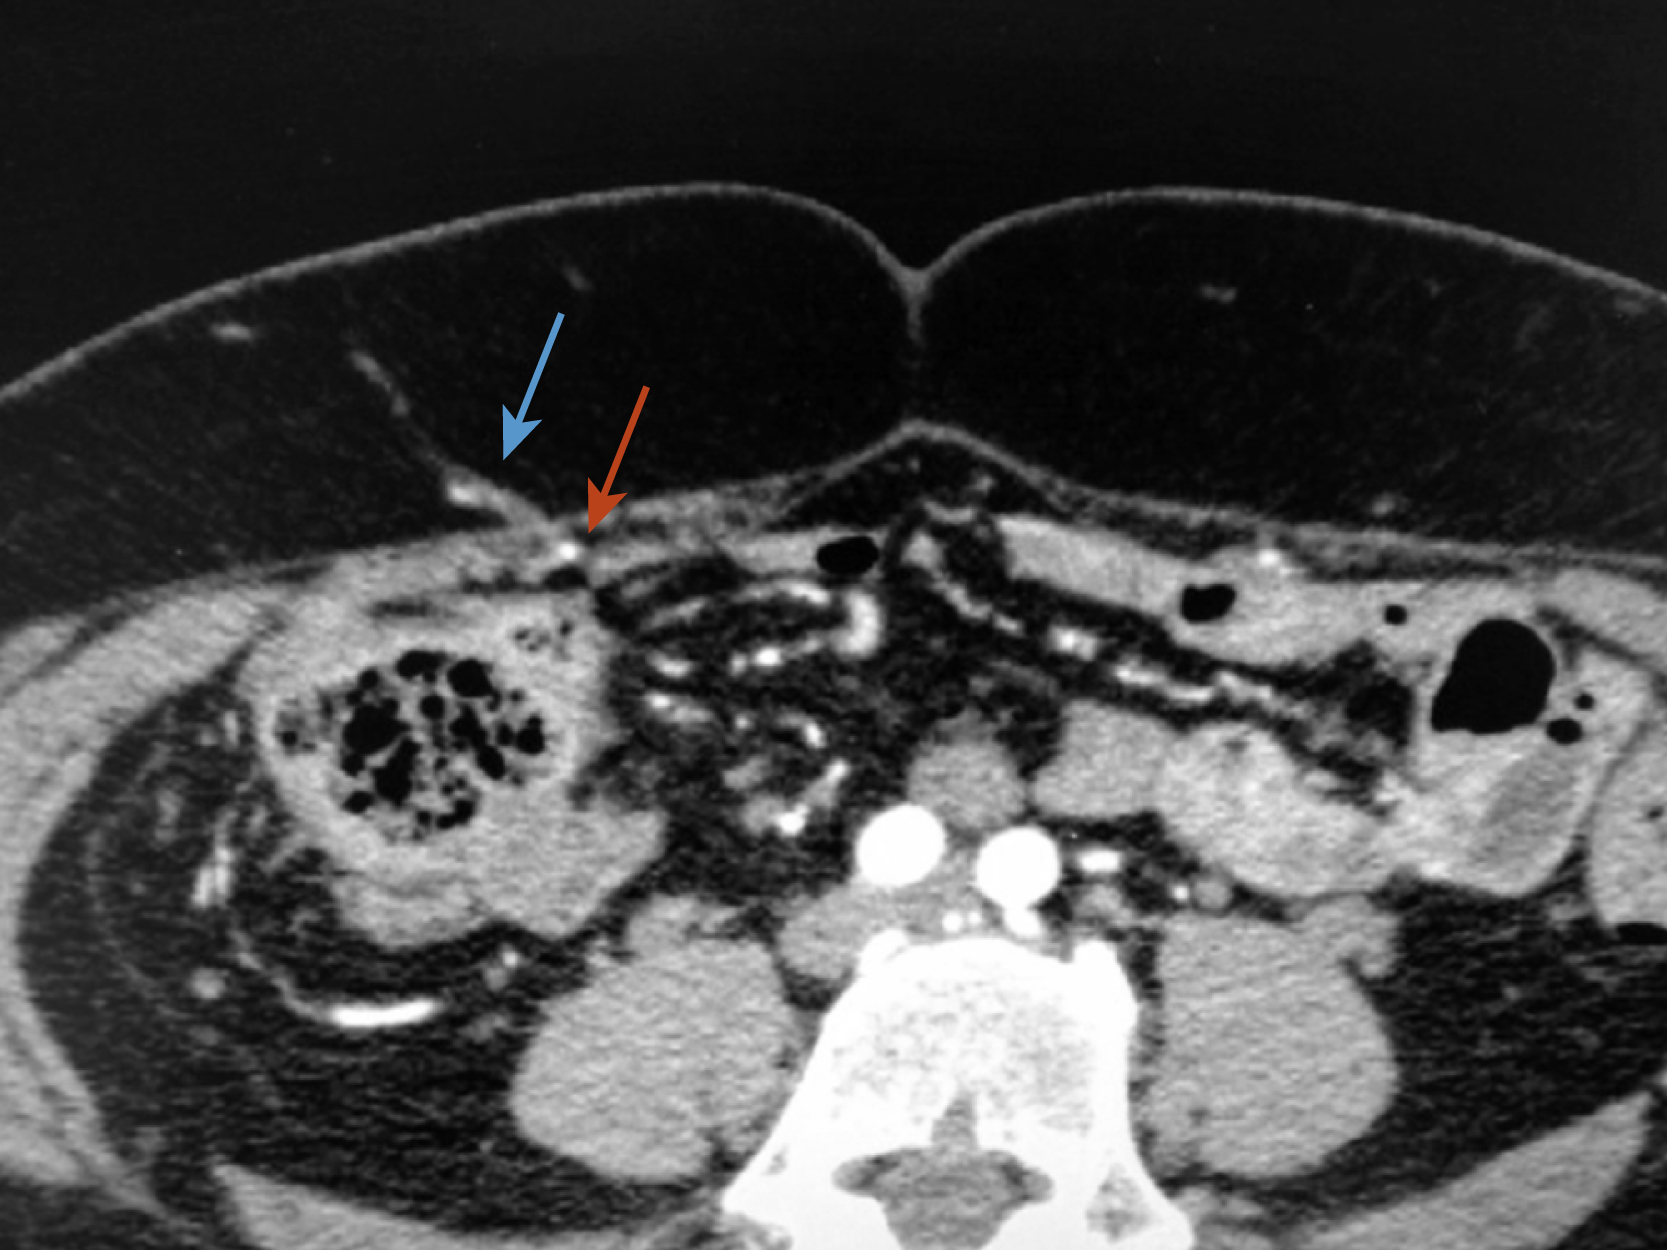

Preoperative imaging is very helpful in defining the pathology and in preoperative planning. Both abdominal computed tomography (CT) and magnetic resonance imaging (MRI) can successfully identify the extent of the abdominal wall defect and the integrity of adjacent musculofascial structures. However, CT angiography (i.e., with intravenous contrast) is superior at delineating the vascular anatomy, especially when planning pedicled flaps or free tissue transfer ( Fig. 40.4 ). An abdominal and pelvic CT scan with oral contrast enables detailed understanding of the wound and intraabdominal contents.